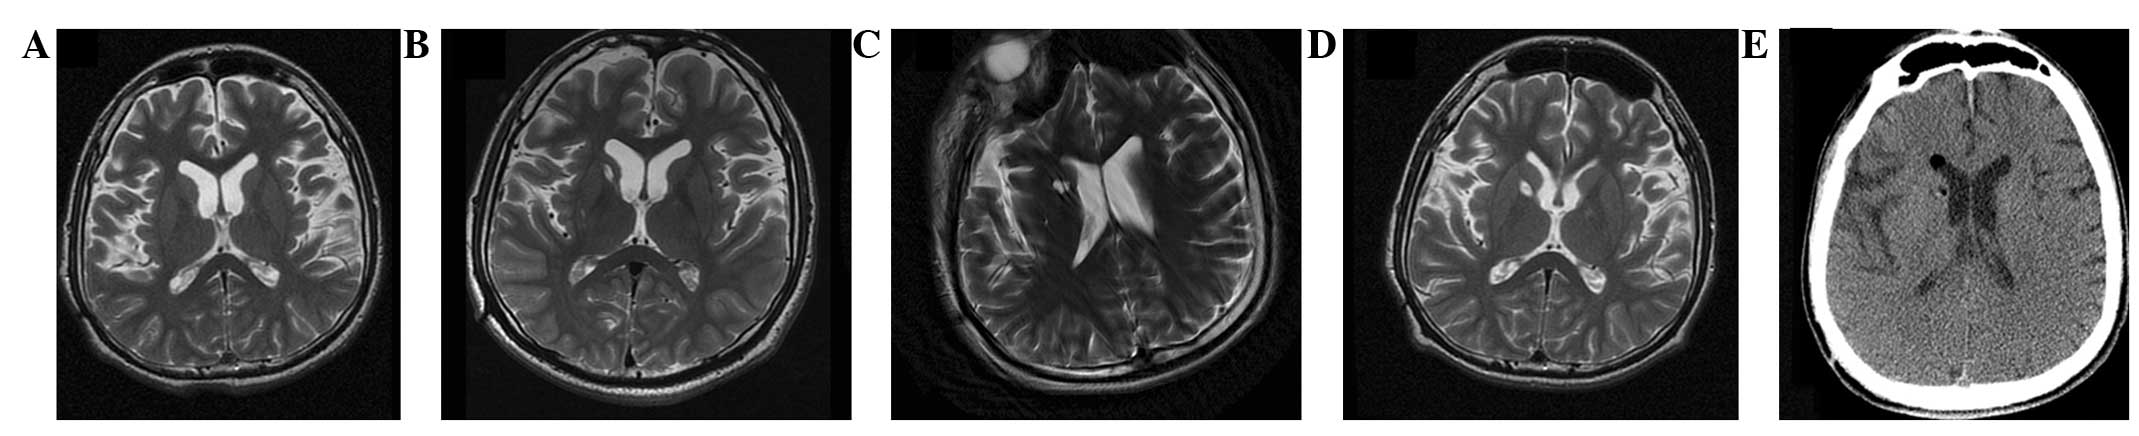

圖2:-T2加權磁共振成像 (MRI)

(A) 術前 MRI 顯示腦萎縮。 (BD)術后1年、3年、4年MRI與術前MRI相比無明顯變化。 (E) 術后3天,計算機斷層掃描顯示沒有出血或水腫。

遺傳分析發現患者DYT1 ( TOR1A )第五外顯子存在突變 (907-909 delGAG) 。他對神經外科手術表現出良好的耐受性,并于4點出院。沒有與細胞植入或外科手術相關的嚴重不良事件。POD時的CT掃描顯示沒有出血或水腫(圖2e)。術后1個月,患者的PTD癥狀開始改善。BFMDMS逐漸增加,從術前的21分別增加到術后1、2、3和4年的18、17、15和13,術后4年改善38.1%(表1)。

CT(圖1b-e)和MRI(圖2b-d)掃描顯示4年隨訪期間沒有顯著變化。 手術前1天(圖1f)和手術后1、2、3和4年(圖1g-j) 獲得18F-FDGPET掃描。術后雙側植入部位豆狀核和丘腦18F-FDG攝取值較術前增加。這一結果表明,自移植以來,葡萄糖代謝逐年略有增加。